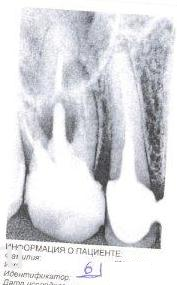

vitankom Опубликовано 20 марта, 2012 Поделиться Опубликовано 20 марта, 2012 Здравствуйте, год назад лечение пульпита шестого верхнего зуба. Коронковая часть зуба значительно была разрушена. Каналы запломбированы, поставлен штифт. Две недели назад на десне (щечная сторона) появилось образование с мутно-белым содержимым. Зубной боли не было и нет.Стоматолог рекомендовал удаление.Просьба прокомментировать, можно ли сохранить зуб? Ссылка на комментарий

Ayrat_zub Опубликовано 20 марта, 2012 Поделиться Опубликовано 20 марта, 2012 там у вас каналы недопломбированы, насколько вижу...возможность перелечивания каналов зависит от врача, финансов и того, что останется после удаления штифта, имхо) Ссылка на комментарий

ger_berra Опубликовано 20 марта, 2012 Поделиться Опубликовано 20 марта, 2012 (изменено) Качество снимка не очень.Если нет перфорации на дне полости,то попробовать спасти Ваш зуб можно,но для этого нужно его полностью "разобрать":снять пломбу,вытащить штифт,перелечить каналы,потом протезирование(культевая вкладка +коронка). Изменено 20 марта, 2012 пользователем ger_berra Ссылка на комментарий